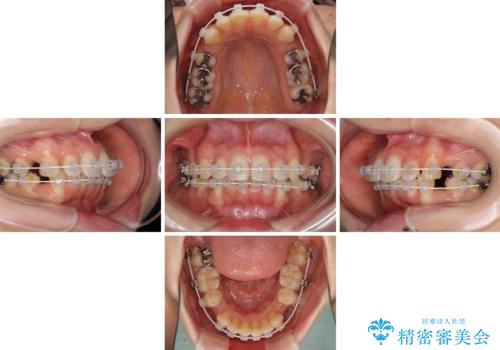

- 審美装置

- 2年8ヶ月

- 10-30回

元々ディープバイトのため、スペースを閉じている期間に上下前歯が接触してしまい、治療期間が想定よりも伸びてしまいました。